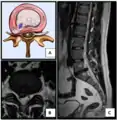

Cervical disc herniation

Herniated disc at C6–C7 level

Cervical disc herniations occur in the neck, most often between the fifth and sixth (C5–6) and the sixth and seventh (C6–7) cervical vertebral bodies. There is an increased susceptibility amongst older (60+) patients to herniations higher in the neck, especially at C3–4.[23] Symptoms of cervical herniations may be felt in the back of the skull, the neck, shoulder girdle, scapula, arm, and hand.[24] The nerves of the cervical plexus and brachial plexus can be affected.[25]